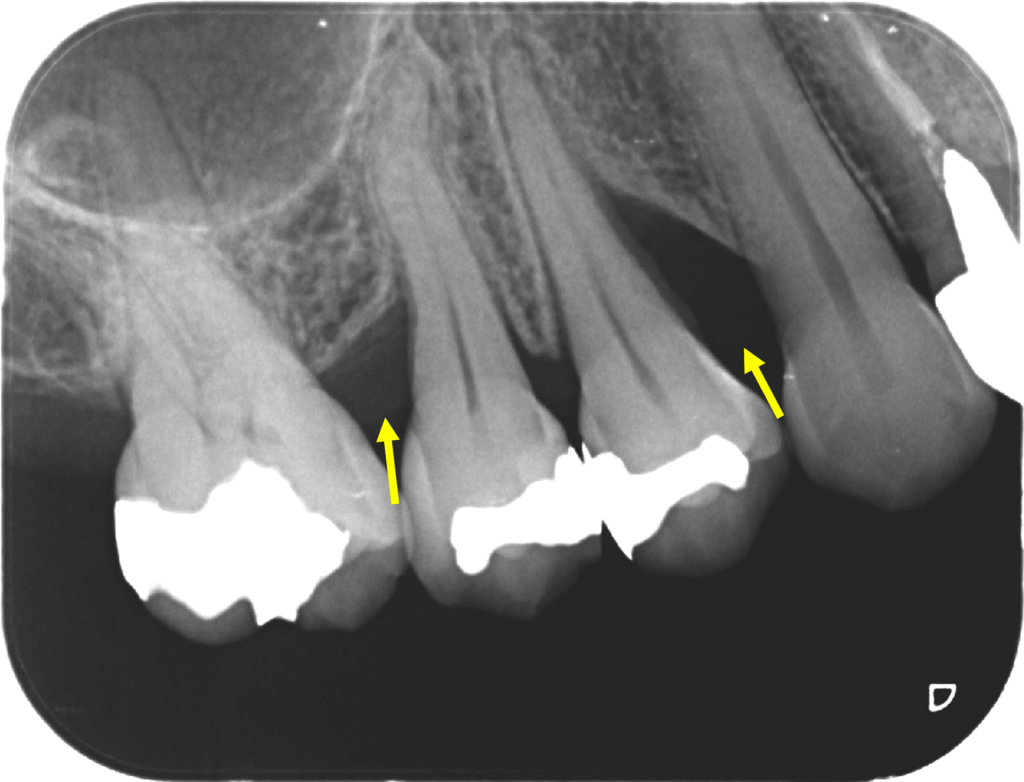

黄色い矢印のところの骨(歯槽骨)が溶けています。

歯周再生材料と人工骨を併用した歯周再生外科を行いました。

外科後2年です。

骨様組織で骨(歯槽骨)が溶けていた部分が満たされていることが確認できます。